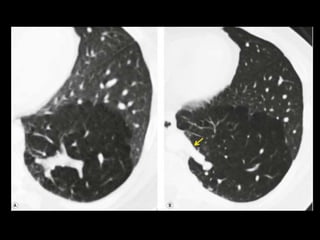

Êmbolo Séptico

TC: nódulos bilaterais mais numerosos nas regiões

Os nódulos podem ser bem circunscritos ou mal

O sinal do vaso nutriz pode estar presente em 60-

Êmbolo Séptico TC: modalidade importante para confirmar a presença de êmbolos sépticos quando a radiografia convencional de tórax permanece negativa; TC: nódulos bilaterais mais numerosos nas regiões periféricas dos pulmões e nas bases; Os nódulos podem ser bem circunscritos ou mal definidos e com frequência apresentam escavações; O sinal do vaso nutriz pode estar presente em 60- 70% dos casos.